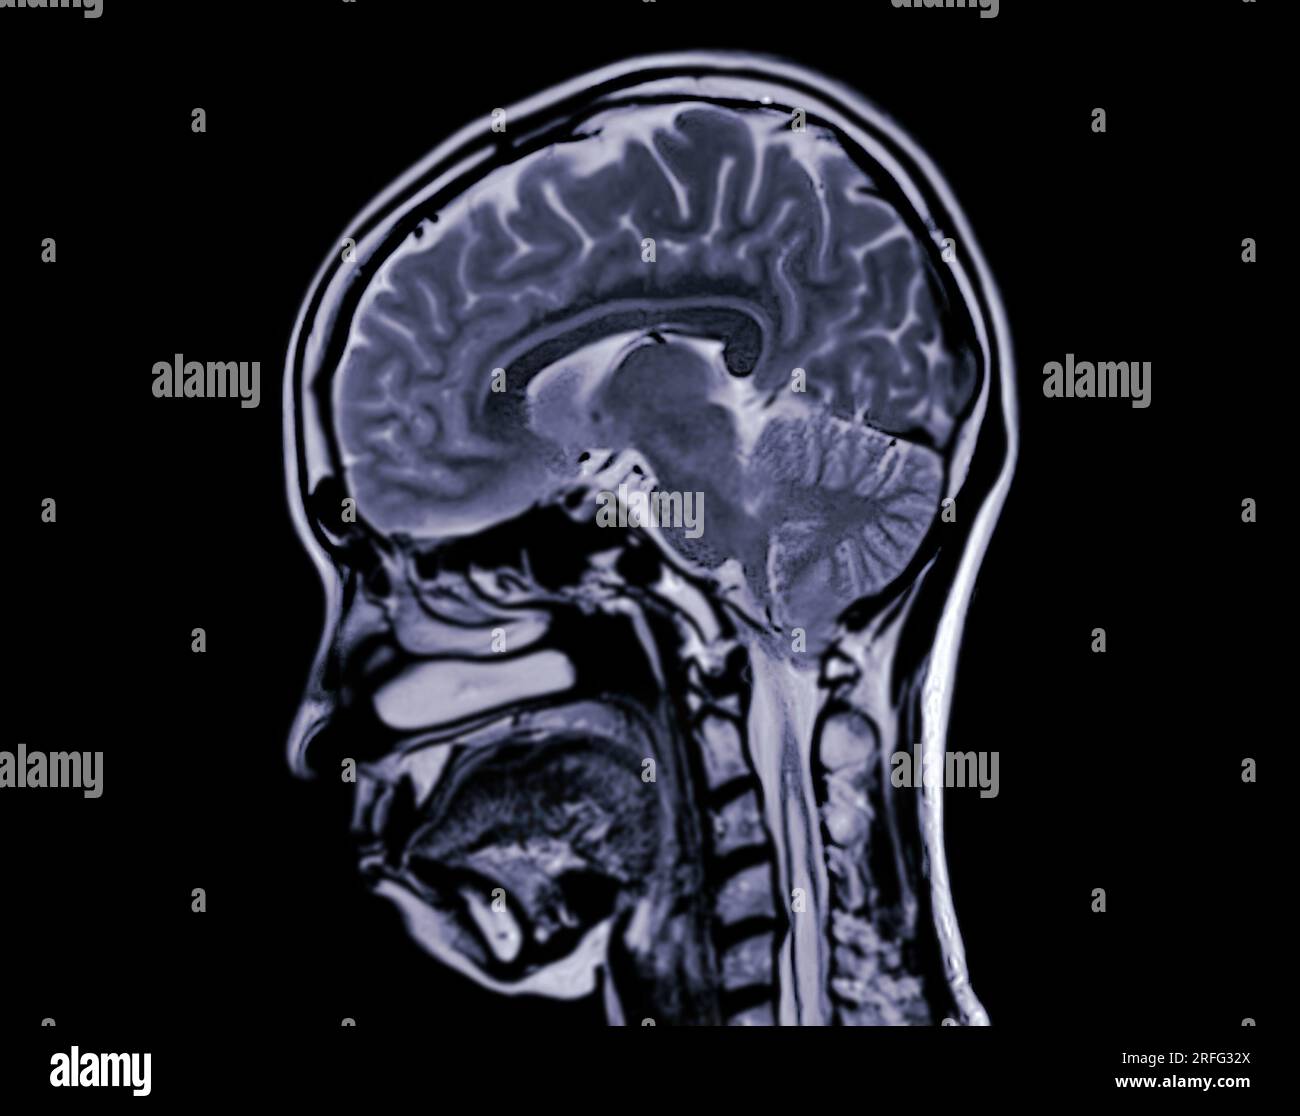

MRI brain scan sagittal plane for detect Brain diseases sush as stroke What Can Mri Brain Detect Functional mri can be used to examine the brain's anatomy and show which parts of the brain are handling critical functions, language and movements. In the case of an ischemic stroke, caused by a blocked blood vessel, an mri can show areas of the brain that are suffering from lack of blood flow. A variant called mr angiography (mra) provides.. What Can Mri Brain Detect.

Selective focus of MRI brain sagittal plane for detect a variety of What Can Mri Brain Detect An mri of the brain can be used to evaluate many symptoms which may be caused by abnormalities in the central nervous system. A head mri is a useful tool for detecting a number of brain conditions, including: In the case of an ischemic stroke, caused by a blocked blood vessel, an mri can show areas of the brain that. What Can Mri Brain Detect.